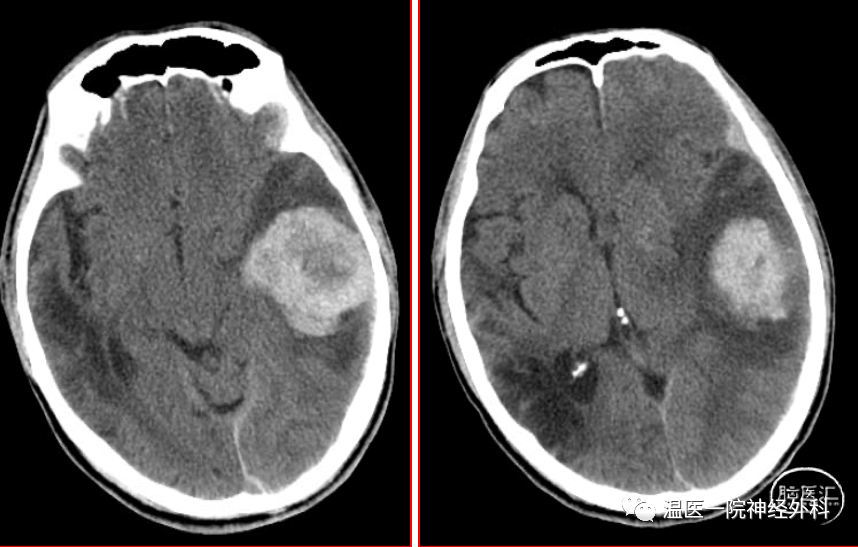

温医一院神经外科病例分享9颅内磷酸盐尿性间叶肿瘤1例

图片尺寸858x547